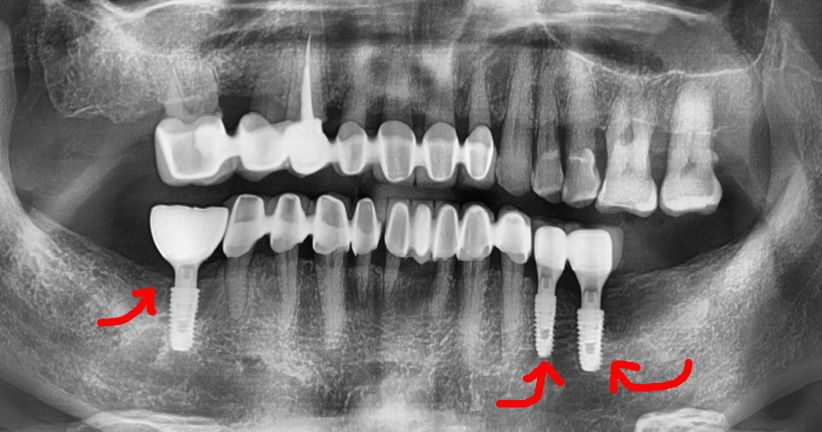

앞서 진단 내용에 따라서, 3개의 고정체를

심은 뒤에 엑스레이를 찍었습니다.

이 분은, 골질의 상태가 그렇게 좋지 않았기에

골 융합 기간을 길게 가져가기로 했습니다.

즉, 회복기간을 충분히 두어 뼈와 단단히

결합이 되었을 때 보철을 올려드릴 예정입니다.

이후, 대략 2개월이 지난 시점으로 치과 에

다시 내원을 하셨으며 골 동요도 측정 후에

지르코니아 크라운을 연결해드렸습니다.